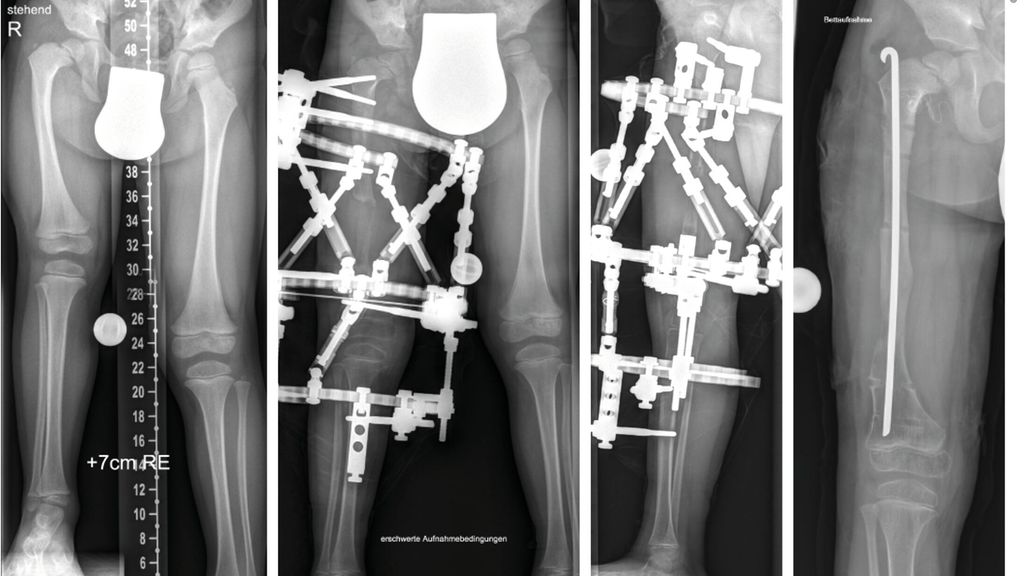

Milde Formen – Typ 1A – zeigen oft nur einen leichten Schenkelhalsvarus und eine verminderte femorale Antetorsion beziehungsweise Retroversion zusätzlich zur Verkürzung. Oft zeigt sich bei diesem Typ auch eine milde subtrochantäre Varusstellung und Sklerose. Mit zunehmendem Schweregrad addiert sich eine azetabuläre Dysplasie, wobei besonders die obere und hintere Überdachung der Hüfte vermindert ist. Beim Typ 1A ist in seltenen Fällen keine vorbereitende Operation erforderlich, insbesondere wenn die Überdachung der Hüfte sehr gut ist und ein CE-Winkel von über 20 Grad vorliegt. Es kann dann direkt mit einer Verlängerung des Femurs begonnen werden. Je nach verwendeter OP-Technik können eine eventuell vorhandene Retroversion und Varusstellung im Rahmen der Verlängerungsoperation akut über eine zusätzliche proximale Osteotomie und Montage an den oberen Teil des Fixateurs adressiert werden. (Abb.1).

Abb. 1: Operative Versorgung eines CFD rechts mit Varusstellung an der Hüfte und subtrochantärer Sklerosierung